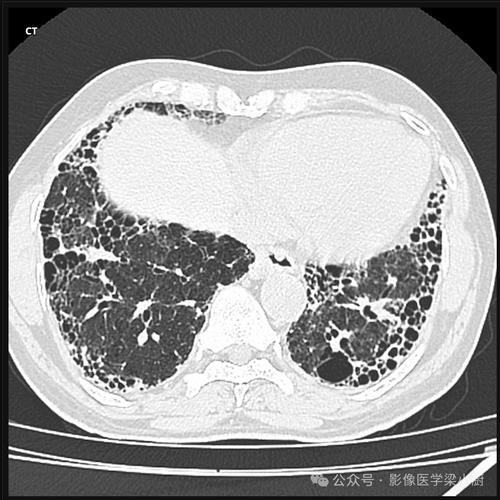

摄影影像的社会应用研究是参考文献中不可或缺的部分,在新闻传播领域,“决定性瞬间”理论(亨利·卡蒂埃-布列松)影响了战地摄影、新闻摄影的实践规范,如《越战摄影与公共舆论》探讨了影像如何塑造公众对战争的态度;在人类学领域,影像民族学方法通过摄影记录文化现象,如《视觉人类学:影像与文化表达》分析了摄影作为文化研究工具的伦理与方法问题;在医学与科学领域,显微摄影、高速摄影等技术推动了跨学科研究,如《医学影像摄影技术手册》详细介绍了医学影像的拍摄标准与应用场景,这些应用文献体现了摄影在不同社会领域的渗透力。